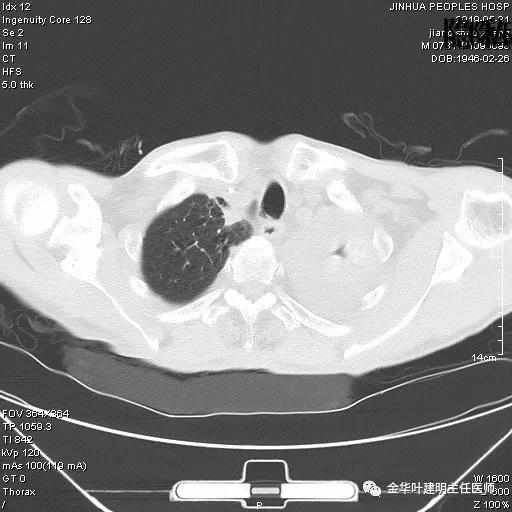

患者,男性,73岁,金华人。因“咳嗽咳痰伴胸闷2月,检查确诊左肺癌1周”入院。气管镜: 气管支气管内较多脓性分泌物,左肺上叶前段管腔新生物,局部活检、毛刷。气管镜病理:(左肺活检)鳞癌。阅胸部CT见左上叶开口处新生物,考虑需左上叶袖式切除及淋巴结清扫。具体CT表现如下:

考虑左侧大量胸腔积液,遂进一步胸部CT检查:

以上是肺窗表现,下面为纵隔窗影像: